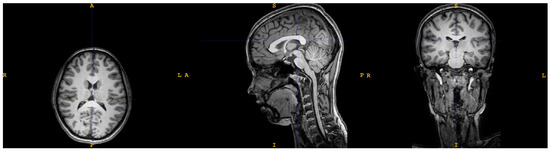

2.1. Magnetic Resonance Imaging (MRI)

2.1.1. Image Processing

| T1 | dMRI | |

| Sequence type | Turbo field echo | Diffusion-weighted single shot spin echo |

| Repetition time | 8.1 ms | 9000 ms |

| Echo time | 3.7 ms | 86 ms |

| Flip angle | 8° | 90° |

| Echo train length | 170 | 59 |

| No. of slices | 240 | 140 |

| B-value | - | 1000 s/mm2 |

| No. of gradient directions | - | 61 |

| Orientation | Sagittal | Axial |

| Acquisition duration | 359 s | 696 s |